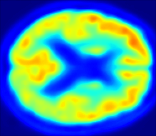

In Fig. 4, the attention maps of the U-PET are shown for multiple examples. On the one hand, the attention map of the skip connection (AttMap skip) highlights details of the brain structure, which is in agreement with the assumption that the network has to transform the specific structures of the MRI scan into the PET modality. On the other hand, the attention gates used for the classification task rather focus on more specific regions. One can observe a trend that the attention maps used for classification tend to highlight regions which have a low uptake in the PET. Since areas with a lower uptake in the PET correspond to areas with lower functional activity (hypometabolism), this focus area of the network seems reasonable with respect to the classification task.